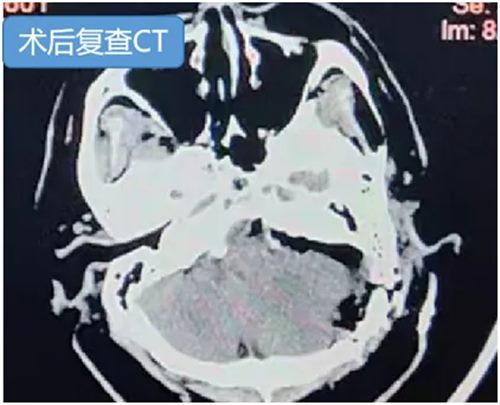

60岁的吴先生持续耳鸣且听力下降就诊,检查发现肿瘤已侵入桥小脑角区,考虑岩尖-天幕型脑膜瘤,因与面神经、听神经紧密缠绕,手术极易引发面瘫、失聪。

手术在神经电生理科孙楹老师的实时监测下进行,术中肿瘤与周边神经血管,尤其是岩静脉粘连紧密,仅历时1个半小时,即实现全切肿瘤,术后患者耳鸣消失,听力正常,无面瘫、面部麻木等不良反应。